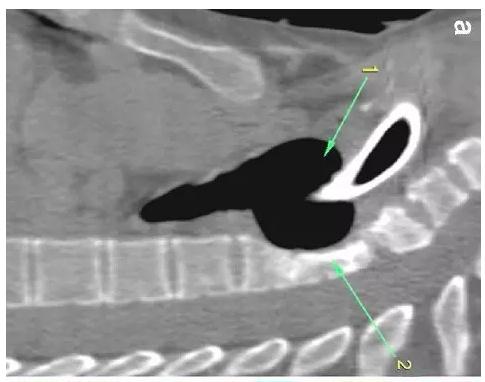

胸部CT顯示氣切套管氣囊周圍氣管擴(kuò)張,胸1-4椎體前部受到侵蝕(下圖a-c)。

患者入住我院前行胸MRI已經(jīng)發(fā)現(xiàn)類似表現(xiàn)(圖d),當(dāng)時(shí)診斷為骨髓炎。

下圖箭頭1為氣切套管氣囊緊貼T1-4椎體水平,造成椎體前部受到侵蝕(箭頭2):

作者推測(cè)患者骨質(zhì)吸收、骨髓炎與氣切套管氣囊過度膨脹有關(guān),為氣囊過度膨脹造成椎體血流灌注降低所致。在我院住院期間,我們也發(fā)現(xiàn)高氣囊壓力才能防止漏氣。經(jīng)食道內(nèi)鏡檢查未發(fā)現(xiàn)氣管食管瘺。